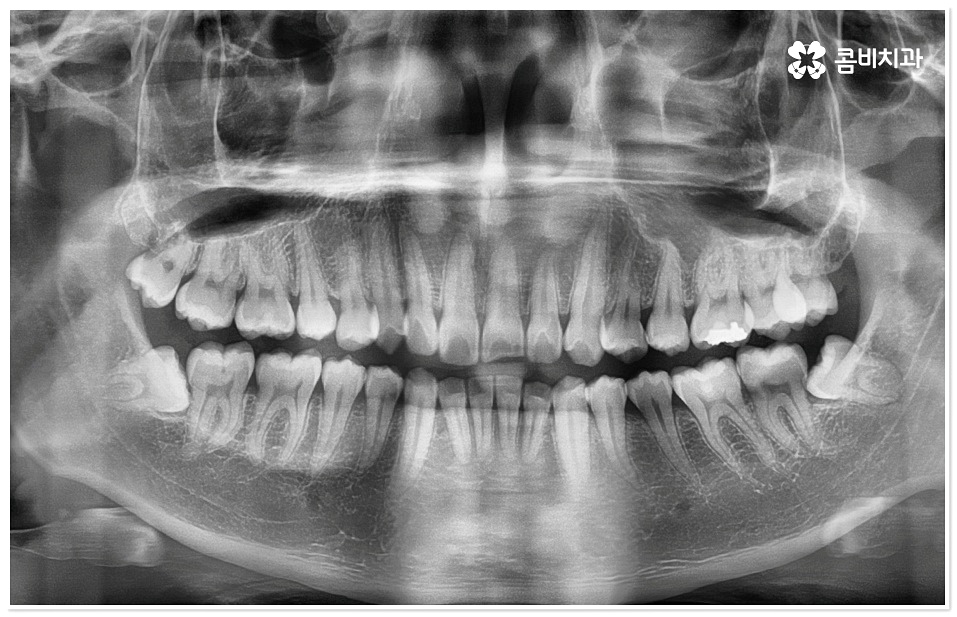

교정 치료란 특수한 장치를 이용해 치아를 원하는 방향으로 이동시켜 치아 배열과 교합을 올바르게 개선해 주는 과정으로 각자의 구강 구조가 다 다르기 때문에 정밀 검사를 통해 환자분들 각각의 치아 모양과 각도, 위치, 교합 뿐 아니라 잇몸 건강 상태 및 상악과 하악의 관계와 같은 구강 내 상황과 함께 입술, 전체 안모 등 대칭과 균형의 측면에서 모든 부분을 다각적이고 입체적으로 분석한 후 세밀한 맞춤 계획을 수립하는 것이 중요할 수 있는데요.

그러므로 3D CT와 같은 정밀 검진 장비와 3D 모르페우스와 같은 시스템을 갖추고 다양한 경험과 노하우를 바탕으로 정확한 진단 및 섬세한 플랜을 세울 수 있는 치과를 잘 알아보고 덧니치아교정 치료를 진행하실 필요가 있어요.